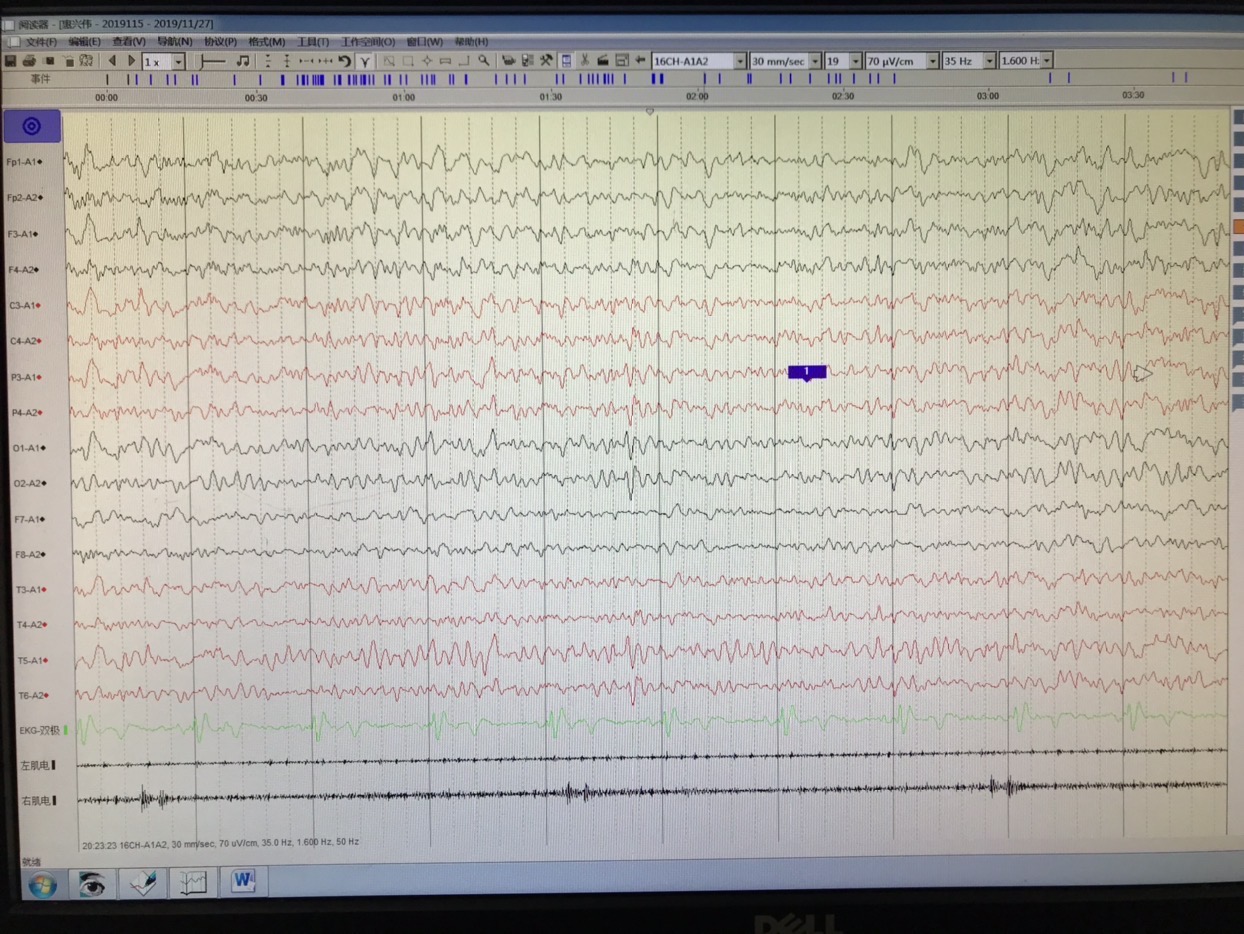

长程视频脑电监测提示左侧中央区、顶区、后颞区见中等量低-中-高波幅痫样放电。